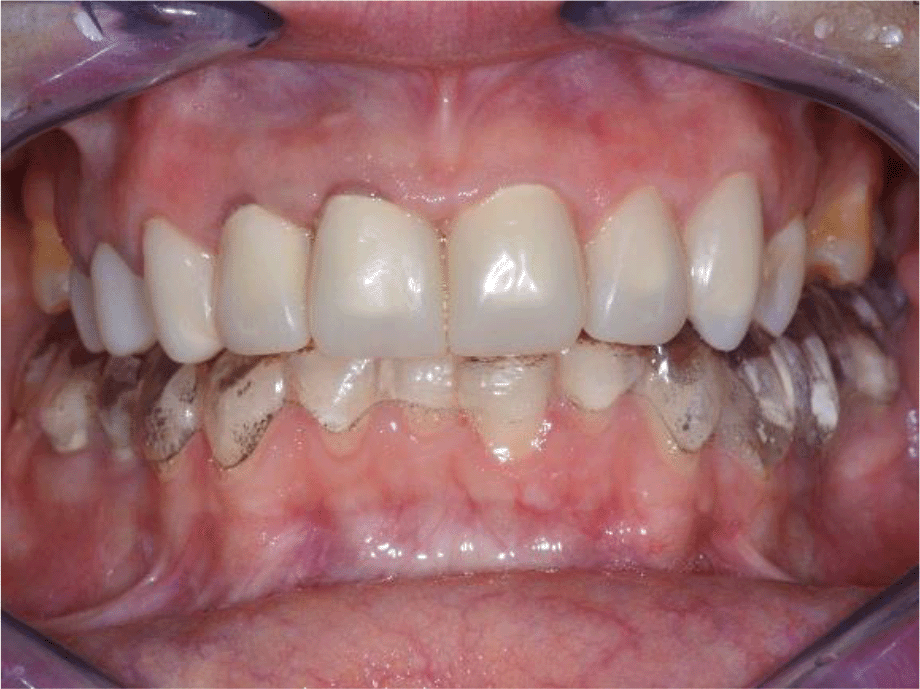

Intraoral examination of the upper jaw revealed a metal-ceramic construction on 13, 12, 11, 21, 22, 23, 24, missing 18, 16, 25, 26. The metal-ceramic construction was made 13 years ago, and was in good condition except for small fractures of the ceramic on the palatal surface and palatal staining of the gingiva by the metal base. The distal available teeth were medialized (Figures 1 and 2).

Figure 1. Initial clinical situation.

On the lower jaw, an advanced phase of abrasion (Attritio dentis cum abrasione) of the frontal teeth was established, reaching the dentin area. Defects of the dentitions were solved with ceramic restorations of 35, 36, 37 on the left and 45, 46 on the right. The occlusal plane was incorrect – the lower frontal teeth were higher. There was a deep overlap of the lower frontal teeth in central occlusion (Figures 3 and 4).

Figure 3. Abraded lower teeth and occlusal plane at initial presentation.

Figure 4. Central occlusion shown on initial presentation.